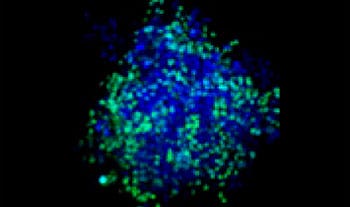

Making the spheroids transparent and imaging them with an FV3000 confocal laser scanning microscope enabled us to image the co-cultured cancer spheroids at depth. Staurosporine treatment increased the number of dead cells in a dose-dependent manner (Fig. 2*1). Three-dimensional analysis is required to determine which cells are dead and how many dead cells there are in a three-dimensional mass.

Figure 2. Drug response in co-culture spheroids

Figure 2. Drug response in co-culture spheroids*1

The Hoechst33342 signals enabled us to recognize the nuclei. All cells were classified into two groups based on the presence or absence of an EGFP signal—EGFP positive (HeLa cells) and EGFP negative (A549 cells). The cells in these two groups were further divided according to the presence or absence of dead cell signals (TO-PRO3, red) for a total of four groups (Fig. 3*1). The percentage of live to total cells of both A549 and HeLa cells was calculated and plotted (Fig. 4). The results showed that HeLa cells were more sensitive to staurosporine than A549 cells.

Using NoviSight™ software, it was possible to classify the cell types contained in each co-culture cancer spheroid and analyze cell-type-specific drug responsiveness.